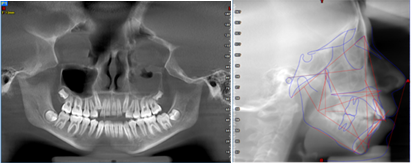

Se prescribió un nuevo examen tomográfico en el que se pudo constatar que se cumplió el objetivo de tratamiento, ya que se consiguió la descompresión de la zona retrodiscal dando lugar a la formación de un pseudodisco que compensó el adelantamiento discal bilateral existente.

Se pudo observar en la imagen tomográfica (Figura 4) la ATM derecha la neoformación de tejido óseo con una ligera erosión en la zona anterior del cóndilo mandibular (A), mientras que en la ATM izquierda se visualizó la formación de un osteofito el cual se genera en etapas avanzadas durante un cambio degenerativo a más de la formación de tejido óseo (B).

Con el presente caso clínico se concluye que, si es posible conseguir mediante la descomprensión en la zona retrodiscal la neo formación de tejido estimulando una fibrosis y por consiguiente a un pseudo disco, también que un factor clave del éxito terapéutico reside en la educación del paciente y sus familiares orientándolos sobre la condición que adolece.